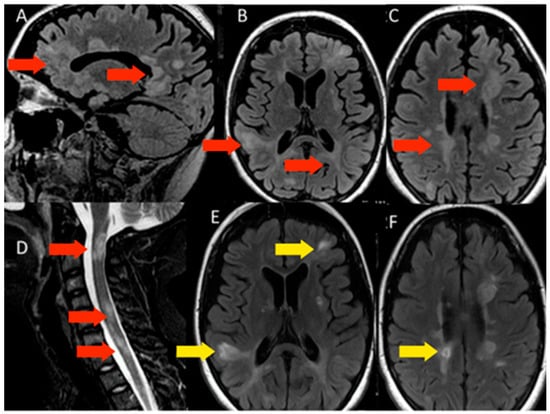

3.1.1. Patient 1

3.1.2. Patient 2

3.1.3. Patient 3